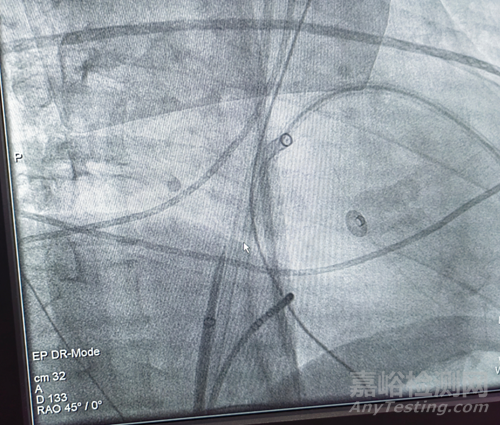

在DSA的引導(dǎo)下,沿導(dǎo)絲將swartz鞘引導(dǎo)至上腔靜脈,撤出導(dǎo)絲,送入心泰醫(yī)療研發(fā)的射頻穿刺針,通過與標(biāo)準(zhǔn)房間隔穿刺術(shù)相同的方法定位穿刺點(diǎn),經(jīng)DSA和體表超聲確認(rèn)后釋放射頻能量完成組織刺破。

患者在三維標(biāo)測輔助下進(jìn)行導(dǎo)管射頻電生理手術(shù),需經(jīng)卵圓窩置入兩根導(dǎo)管,因此使用射頻穿刺針先后兩次對卵圓窩上兩個(gè)不同點(diǎn)位進(jìn)行了穿刺,兩點(diǎn)穿刺均一次成功,后續(xù)電生理手術(shù)也順利完成。

▲第二個(gè)點(diǎn)位穿刺后造影